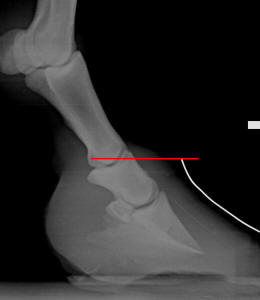

When looking at a lateral radiograph of a horse’s foot, if

the exact location of the top of the hoof wall (hairline) has been marked with a

radiopaque paste or object, there is a measurable distance between the

“elevation” of the top of the hoof capsule and the top of the coffin bone.

Veterinarians and farriers typically refer to this measurement as the CE

(coronet-to-extensor process

distance).

Cross-section of a stillborn foal’s foot. The CE is near zero—the hairline is

almost level with the top of the coffin bone. Photo

reprinted from the book Care and Rehabilitation of the Equine Foot, P.

Ramey.

In newborn horses, and in the healthiest examples of adult

horses, the CE measurement will be near zero. In other words, the top of the

coffin bone will be level with (or within 1/2-inch of) the top of the hoof

capsule (hairline). This “high” (actually normal) bone position allows the

overall hoof length to be very short and compact (usually around 3-3 ½-inches

long at the toe), while still having room for a thick, strong, robust sole

beneath the bone and sensitive tissues.